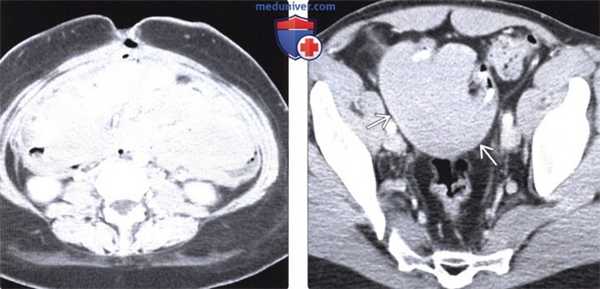

(Слева) На аксиальной КТ с контрастным усилением, выполненной молодой женщине с синдромом Гарднера два года спустя после тотальной колэктомии, определяется фиброматоз брыжейки (десмоидная опухоль) с тотальным поражением брыжейки тонкой кишки. Десмоидная опухоль занимает практически весь объем брюшной полости.

(Справа) На аксиальной КТ с контрастом визуализируется однородное, практически не накапливающее контраст объемное образование в полости таза, обрастающее ближайшие к нему петли кишечника. Это образование является де-смоидной опухолью. Резекция таких опухолей, обрастающих кишечник на большом протяжении, крайне сложна.

Десмоидная опухоль. У пациента в анамнезе имеются сведения о тотальной колэктомии в связи с синдромом Гарднера.

(а, б) На аксиальных КТ-срезах, отражающих венозную фазу контрастирования, определяется минимально усиливающееся при контрастировании объемное образование с четко очерченными краями, находящееся в брыжейке тонкой кишки.

(в) На корональной КТ в венозную фазу контрастирования визуализируется объемное образование в брыжейке тонкой кишки, незначительно накапливающее контраст, без инфильтрации прилежащих органов. Десмоидная опухоль. У пациента в анамнезе — тотальная колэктомия в связи с семейным аденоматозным полипозом.

(а, б) На аксиальном (а) и корональном (б) КТ-срезах, полученных в венозную фазу контрастирования, визуализируется крупное объемное образование в брыжейке, минимально накапливающее контраст (стрелки). Образование имеет размытые края в своей верхней части, а также тяжи, протягивающиеся в прилежащую брыжеечную жировую ткань (указатели).

(в, г) На Т1 взвешенной (в) и Т1 взвешенной (г) аксиальных МР-томограммах, определяется гипоинтенсивное объемное образование в области таза без инфильтрации рядом расположенных органов.

(д) На аксиальной Т1 взвешенной МР-томограмме, полученной в портальную фазу контрастирования, определяется неравномерно накапливающее контраст объемное образование в области таза.